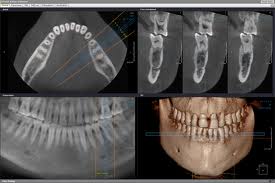

Cone Beam X-rays are a 3 dimensional X-ray of the structures of the mouth. It is similar to a cat scan but fortunately is much lower (25 to 40 times lower) in radiation then a CAT scan. The Cone Beam X-ray is useful in evaluating the amount and quality of bone for dental implants. The software of CEREC is interfacing with cone beam X-ray software and enabling the planning and coordination of implant placement with the position of the final crown and fabrication of the abutment. View the Journal Article that Dr Edwards was a co-author in that showcased Cone Beam X-rays.

We are pleased to add to our Digital X-ray technology a Vatech Cone Beam CT X-ray (CBCT). This is a 3 dimensional X-ray that is very low in radiation but high in diagnostic value. It is very useful in implant planning and surgery and in many other situations. Click on the link below to learn more about our Digital X- Rays.

Digital X-rays can be enhanced and magnified and are easily seen by the patient to help understand their diagnosis and conditions. The digital panoramic X-ray shows structures not seen with small X-rays, such as the sinuses, the jaw joints, impacted wisdom teeth and many other conditions. Digital X-rays are also very easy to transfer to specialists or other dentists. We tailor the need for X-rays to each condition and patient. Many of our healthy patients are having X-rays only every two years.